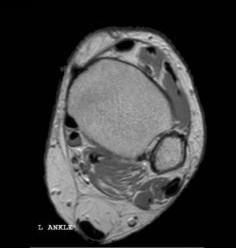

ankle.jpg (6387 bytes)

In this case an overlay image is superimposed on the MR image.

Click here to display/hide overlay